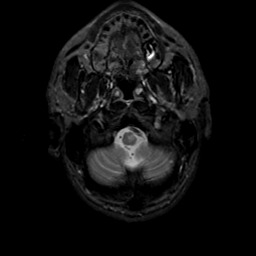

MR Study #22, December 1, 1991 -- Slice #4

[Home][Help][Clinical][Tour 1][Tour 2] Slice 4